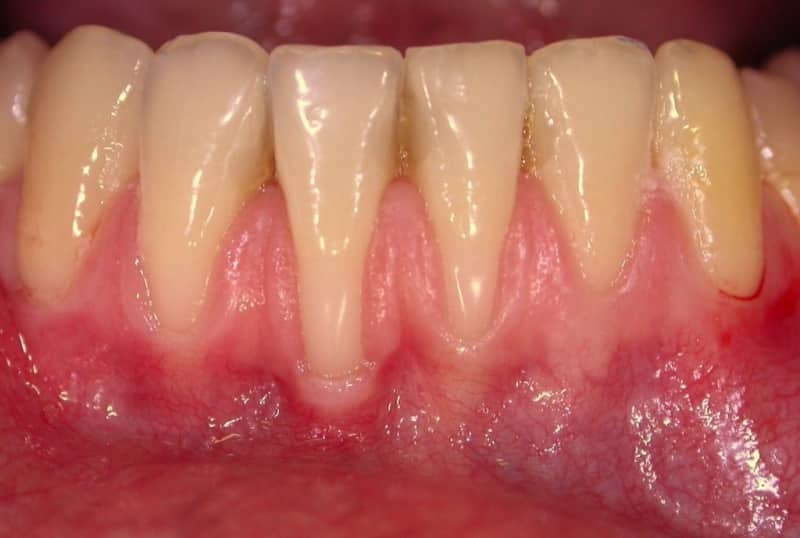

Пародонтоз — это заболевание, которое характеризуется прогрессирующим разрушением тканей, окружающих зубы. Врачи отмечают, что на начальных стадиях пародонтоз может проявляться незначительными симптомами, такими как покраснение и отечность десен. Однако по мере развития болезни наблюдаются более серьезные изменения. На фотографиях, иллюстрирующих это заболевание, можно увидеть отступление десен, образование карманов между зубами и деснами, а также появление зубного камня. Врачам важно подчеркнуть, что своевременная диагностика и лечение могут значительно замедлить прогрессирование пародонтоза и сохранить здоровье зубов. Визуальные признаки заболевания могут варьироваться, но в любом случае требуют внимания специалиста для предотвращения серьезных осложнений.

| Рецессия десны (оголение корней) | Десна опускается, обнажая корни зубов, которые могут выглядеть длиннее обычного. | [Изображение рецессии десны] |